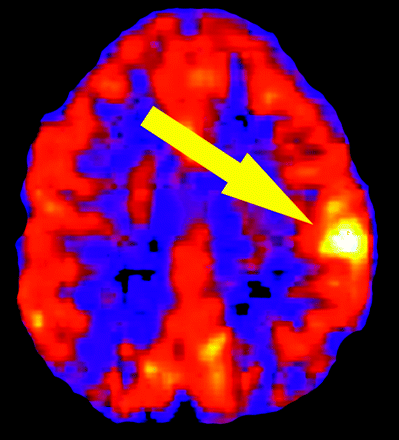

Because it is not subject to artifacts due to the recirculation of tracer, ASL is well suited for the serial assessment of brain perfusion in the setting of acute stroke and can provide important prognostic information regarding reperfusion. Restoration of flow to regions of the ischemic core or penumbra can be seen as high signal intensity on ASL following spontaneous recanalization of clot, administration of systemic or transcatheter thrombolytics, or extracranial-to-intracranial bypass. These areas of reperfusion can be distinguished from stagnant intravascular spin-label because they often correspond to anatomic structures such as the basal ganglia, thalamus, insula, or a cortical gyrus. Figure 2 demonstrates focal hyperperfusion in the left middle cerebral artery (MCA) territory 12 hours following the administration of systemic thrombolytic agents, whereas spontaneous reperfusion of an infarcted territory is shown in Fig 3.

Reperfusion. An 80-year-old woman presenting with right hemiparesis met the criteria for systemic thrombolytics. ASL CBF map acquired approximately 12 hours after tissue plasminogen activator administration reveals localized hyperperfusion within the left MCA territory (arrow). Perfusion is otherwise preserved throughout the left hemisphere.